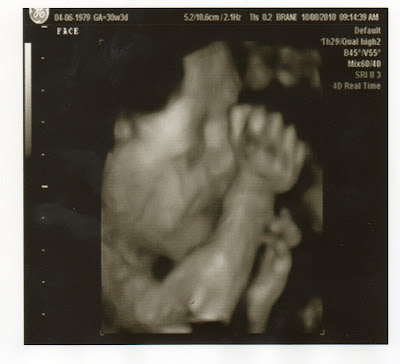

Sneak Peak At Baby Coy Anthony Willis

Today, Chad, Colter, and I went to have a 4D Ultrasound of Baby Coy. These are tricky because the baby has to be cooperating to get good pictures, and today Baby Coy was not in the mood to have his picture taken! So, we only got a few pictures, and were not charged for the 4D ultrasound. Here are a few pictures of the better ones. The ultrasound tech said there was not enough fluid around his head to get good pictures, so they are very distorted and the umbilical cord was floating in front of his face the majority of the time. Then at the very end he flipped over completely and we were not able to do anymore pictures. Looks like we will just have to wait....only 10 more weeks! Can't wait to meet you Baby Coy!